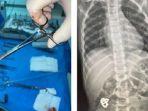

PROHABA.CO, RIYADH – Satu tim dokter berhasil mengeluarkan gelang yang berpotensi berbahaya dari perut seorang anak berusia enam tahun.

Satu tim spesialis medis di Rumah Sakit King Abdulaziz di Jeddah, Arab Saudi, melakukan operasi selama dua setengah jam.

Akhirnya anak itu berhasil diselamatkan.